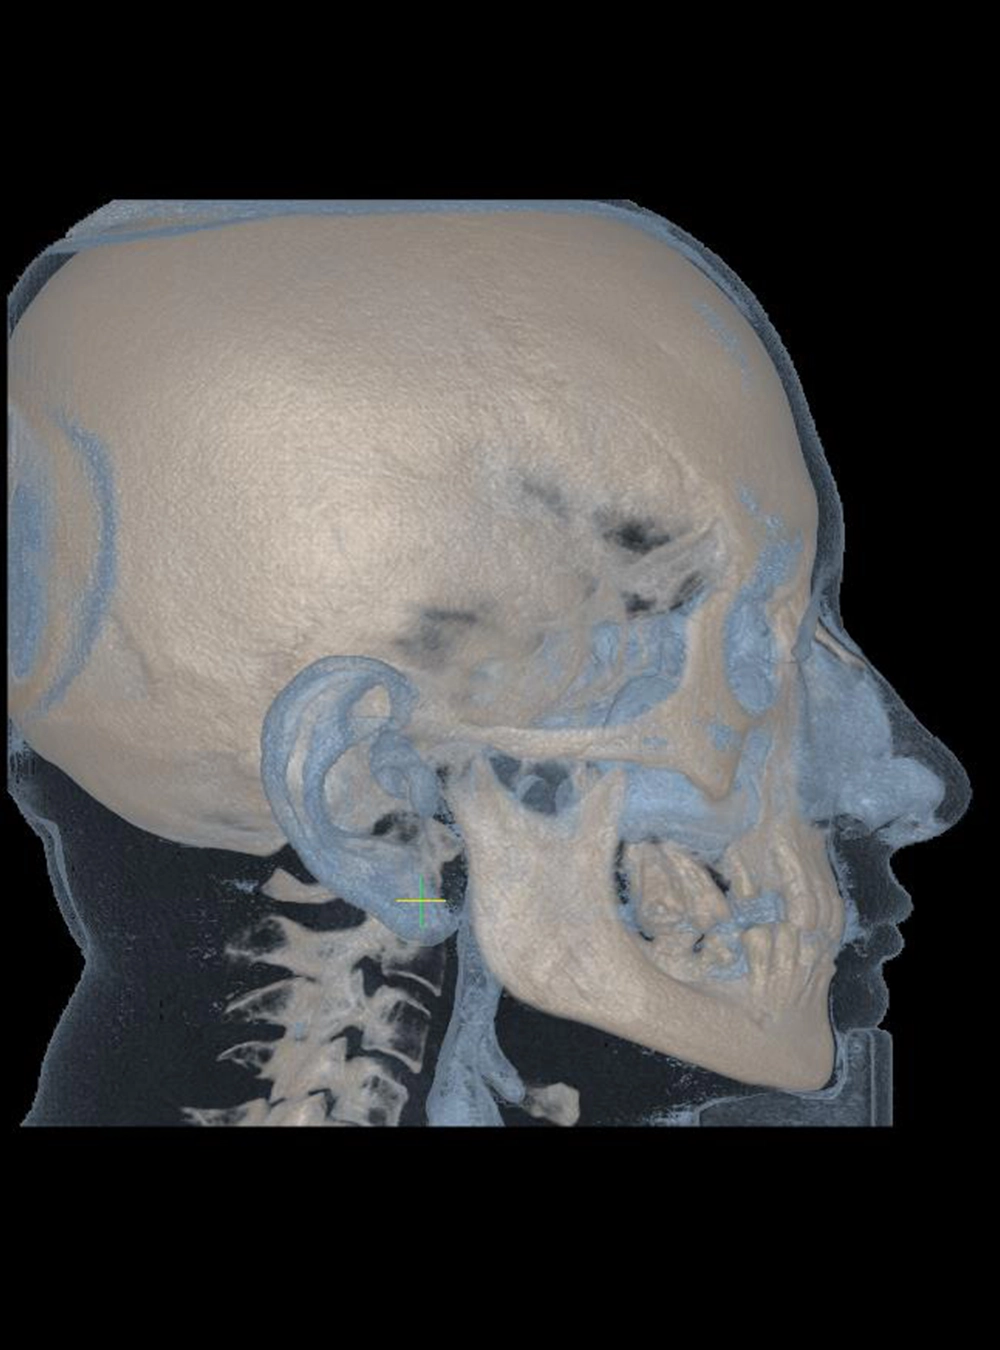

Tomografía Volumétrica

Cone Beam (USB o CD)

Estudios 3D

• Tomografía Completa Cone Beam